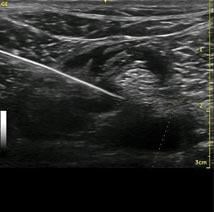

Image courtesy of Soundwaves LLC

MSK ultrasound allows physicians to visualize muscles, tendons, ligaments, nerves and joints in an office setting for diagnostic purposes as well as precisely guided injection procedures.

Procedures that we were not able to do in office, such as hip intra-articular injections and shoulder bicipital groove injections, we can now do with confidence," added Voglino.